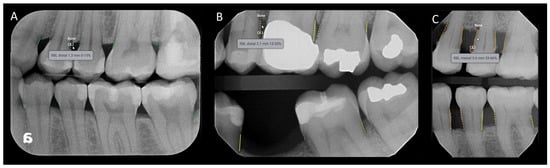

2.3. The Deep Learning Software, Definition of RBL Used, and Reference Standard